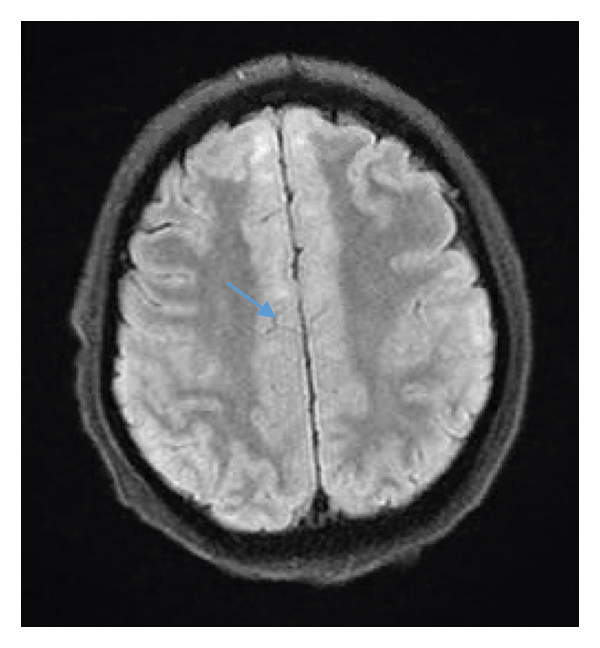

A 44-year-old Hispanic male from Mexico presented to the emergency department for progressive nasal congestion, rhinorrhea, ear fullness, facial swelling, and sore throat that has been ongoing for 2 months. He also noted gradual vision loss of his right eye and intermittent bloody discharge from both the nostrils. Bedsides, rhinoscopy showed swelling of the right nare and nasal turbinates along with small blood clots without active bleeding. A maxillofacial computed tomography (CT) scan showed phlegmonous change about the right lamina papyracea with an erosive change. Also shown was destruction and soft-tissue swelling that extends along the medial border of the right orbit (Figure 1). Biopsy of the right nasal vestibule was diagnostic for extranodal NK/T-cell lymphoma nasal type. The atypical cells were positive for CD2, CD3, CD4, CD56, CD43, and Bcl-2 and negative for CD5, CD7, CD8, CD10, CD20, CD30, and BCL-6. In situ hybridization was positive for the Epstein–Barr encoding region (EBER). Bone marrow biopsy showed a normocellular bone marrow with trilineage hematopoiesis. Additional imaging with magnetic resonance imaging (MRI) of the head showed a vague enhancement over the frontal convexities. EBV DNA PCR in the blood was 4.90 log10 IU/mL (equivalent to 79,792 IU/mL). He was started on a modified SMILE (m-SMILE) regimen consistent of methotrexate 2 g/m2 given on day 1, etoposide 100 mg/m2, ifosfamide 1500 mg/m2, dexamethasone 40 mg/d given on days 2 to 4, and pegasparagase 2000 U/m2 given on day 8 of a 28-day cycle (Figure 2). He developed acute right-sided complete vision loss; magnetic resonance imaging of the orbits showed increased enhancement of the optic nerve sheath with a complex edema suspicious for optic nerve invasion. The case was discussed at an ENT oncology and other multidisciplinary oncology conferences; the decision was made to proceed with the same chemotherapy regimen. The patient then received prophylactic intravitreal methotrexate of the left eye. He completed his second cycle of m-SMILE, and a follow-up positron emission tomography-computed tomography (PET/CT) scan showed good response (Figure 3(a)). Methotrexate dose had to be reduced 50% on the third cycle of m-SMILE due to kidney injury. He subsequently received 4 more cycles of m-SMILE with 25% dose reduction of chemotherapeutic agents due to prolonged cytopenia from previous cycles. His EBV DNA PCR turned undetectable after the first cycle and remained so after the final (6th) cycle. A restaging PET/CT scan showed good response with faint residual disease in the paranasal sinuses and sinonasal cavity (Figure 3(b)). One month after he completed his last cycle, he developed new-onset severe headache, confusion, and shortness of breath. He was admitted to the emergency department where a CT scan of the head showed diffuse cerebral and cerebella edema. MRI of the brain with intravenous contrast revealed multiple focal cortical and subcortical signal abnormalities, with extensive gyral swelling involving the frontal, anterior parietal, and bilateral temporal lobe. Subtle enhancement in the sulci of the high frontoparietal region, particularly at the central sulcus, was noted (Figures 4 and 5 ). Cerebrospinal fluid examination was positive for CD 56+ cells and aberrant atypical lymphocytes. EBV DNA PCR was 14,800 IU/mL. His course was later complicated by respiratory failure and cerebellar tonsillar herniation; he subsequently succumbed after 19 days of hospitalization.

One of the most common presentations is nasal obstruction followed by bloody rhinorrhea. B symptoms, including prolonged fevers and weight loss, can also be present in up to 50% of the cases [3, 11]. Ocular involvement represents mainly uveitis/vitritis; orbital infiltration has been reported in the literature as complication of NNKTL [12].CNS involvement has been reported as being a primary involvement as well as a progression or invasion from an existing primary tumor, which is mainly in the nasopharynx. In both instances, the prognosis is dismal and the overall survival drops from 20 months to 7 months [13]. Treatment of NNKTL depends on the stage of the disease at diagnosis. It usually involves chemotherapy, radiation, and bone marrow transplantation [14]. In this case, the patient had limited-stage disease (IE).This case was presented in the tumor board and ENT oncology sessions. The review of the questionable slight enhancement on the initial staging MRI of the head was deemed not significant and unlikely representing CNS disease. The plan was sequential therapy with chemotherapy (modified SMILE regimen) followed by radiation therapy, the so called “sandwich” approach. The decision was to proceed with regular-dose methotrexate (2 g/m2). The higher dose of 3 g/m2 has a better CNS penetration [15]. Radiation was supposed to be given at a total dose of 50 Gy to the involved paranasal sinuses via intensity-modulated radiation therapy (IMRT) over 5 to 6 weeks. Compliance to clinical appointments as well as chemotherapy induced adverse events such as prolonged neutropenia and fatigue delayed the process. A restaging PET/CT scan performed after the 6th cycle did not show any evidence of disease. The last hospital admission was shortly after the restaging PET scan was performed. It was until the patient was readmitted for headache and confusion that the MRI head was performed and showed evidence of leptomeningeal spread, which was late in the course. To note, that patient had complete right vision loss due to right optic nerve invasion by the tumor and received prophylactic intravitreal methotrexate in the left eye. To date, there is no consensus regarding treating ocular involvement as a CNS involvement with high-dose methotrexate, intrathecal methotrexate, or brain radiation.